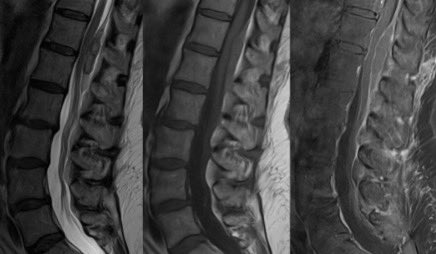

⭐️ Answer: Spontaneous spinal epidural hematoma (no clear risk factor in this case)